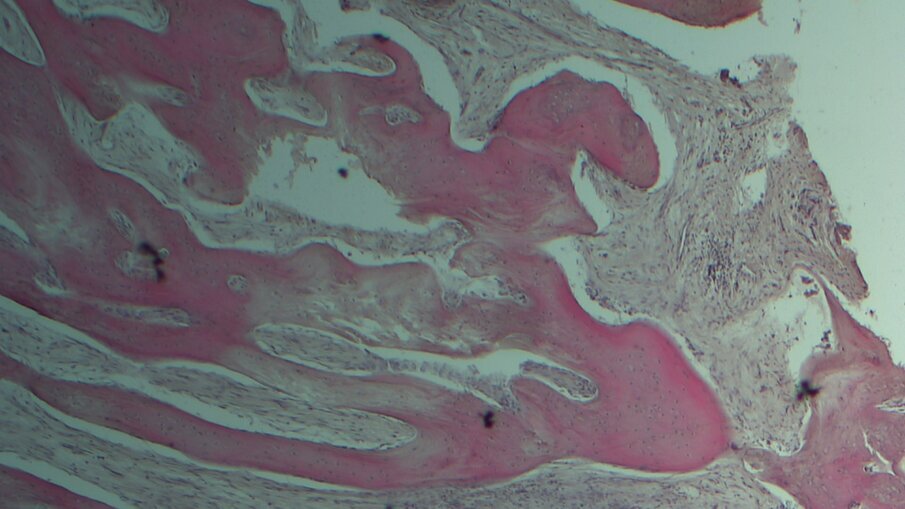

L’esame istologico ha rivelato che il biomateriale era quasi completamente riassorbito. Non erano presenti segni di infezione e la lamina non era staccabile né clinicamente né nelle immagini istologiche. La morfologia ossea mostrava un osso maturo e mineralizzato (Figg. 3, 4). Con riferimento alla larghezza e altezza media della cresta sono stati registrati rispettivamente un guadagno di 2,36 ± 0,69 mm e 3,13 ± 0,90 mm. Non si sono verificate complicanze.